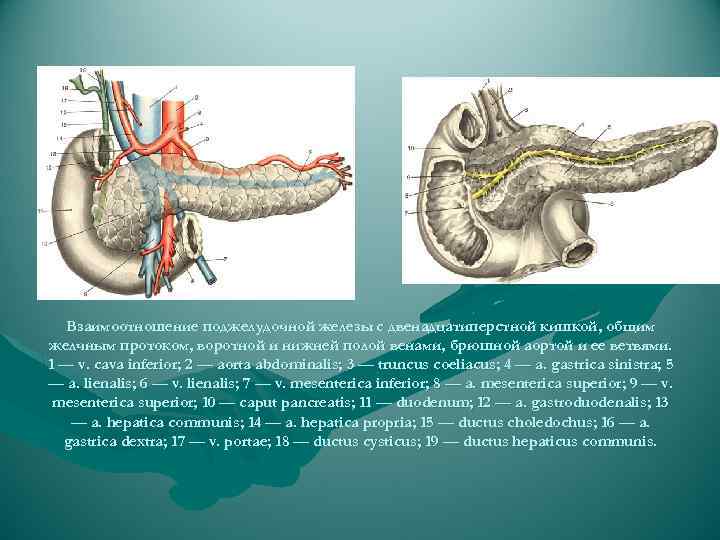

Кровоснабжение головки поджелудочной железы осуществляется из передней и задней артериальных дуг, образованных двумя верхними (из a. gastroduodenalis) и двумя нижними (от начального отдела a. mesenterica superior) панкреатодуоденальными артериями. От каждой из названных дуг в паренхиму головки отходит от 3 до 7 артерий. Тело и хвост поджелудочной железы снабжаются кровью из rr. pancreatici от селезеночной артерии. Отток венозной крови происходит непосредственно в воротную вену и ее главные притоки — vv. lienalis et mesenterica superior.

Кровоснабжение головки поджелудочной железы осуществляется из передней и задней артериальных дуг, образованных двумя верхними (из a. gastroduodenalis) и двумя нижними (от начального отдела a. mesenterica superior) панкреатодуоденальными артериями. От каждой из названных дуг в паренхиму головки отходит от 3 до 7 артерий. Тело и хвост поджелудочной железы снабжаются кровью из rr. pancreatici от селезеночной артерии. Отток венозной крови происходит непосредственно в воротную вену и ее главные притоки — vv. lienalis et mesenterica superior.

Взаимоотношение поджелудочной железы с двенадцатиперстной кишкой, общим желчным протоком, воротной и нижней полой венами, брюшной аортой и ее ветвями. 1 — v. cava inferior; 2 — aorta abdominalis; 3 — truncus coeliacus; 4 — a. gastrica sinistra; 5 — a. lienalis; 6 — v. lienalis; 7 — v. mesenterica inferior; 8 — a. mesenterica superior; 9 — v. mesenterica superior; 10 — caput pancreatis; 11 — duodenum; 12 — a. gastroduodenalis; 13 — a. hepatica communis; 14 — a. hepatica propria; 15 — ductus choledochus; 16 — a. gastrica dextra; 17 — v. portae; 18 — ductus cysticus; 19 — ductus hepaticus communis.

Взаимоотношение поджелудочной железы с двенадцатиперстной кишкой, общим желчным протоком, воротной и нижней полой венами, брюшной аортой и ее ветвями. 1 — v. cava inferior; 2 — aorta abdominalis; 3 — truncus coeliacus; 4 — a. gastrica sinistra; 5 — a. lienalis; 6 — v. lienalis; 7 — v. mesenterica inferior; 8 — a. mesenterica superior; 9 — v. mesenterica superior; 10 — caput pancreatis; 11 — duodenum; 12 — a. gastroduodenalis; 13 — a. hepatica communis; 14 — a. hepatica propria; 15 — ductus choledochus; 16 — a. gastrica dextra; 17 — v. portae; 18 — ductus cysticus; 19 — ductus hepaticus communis.